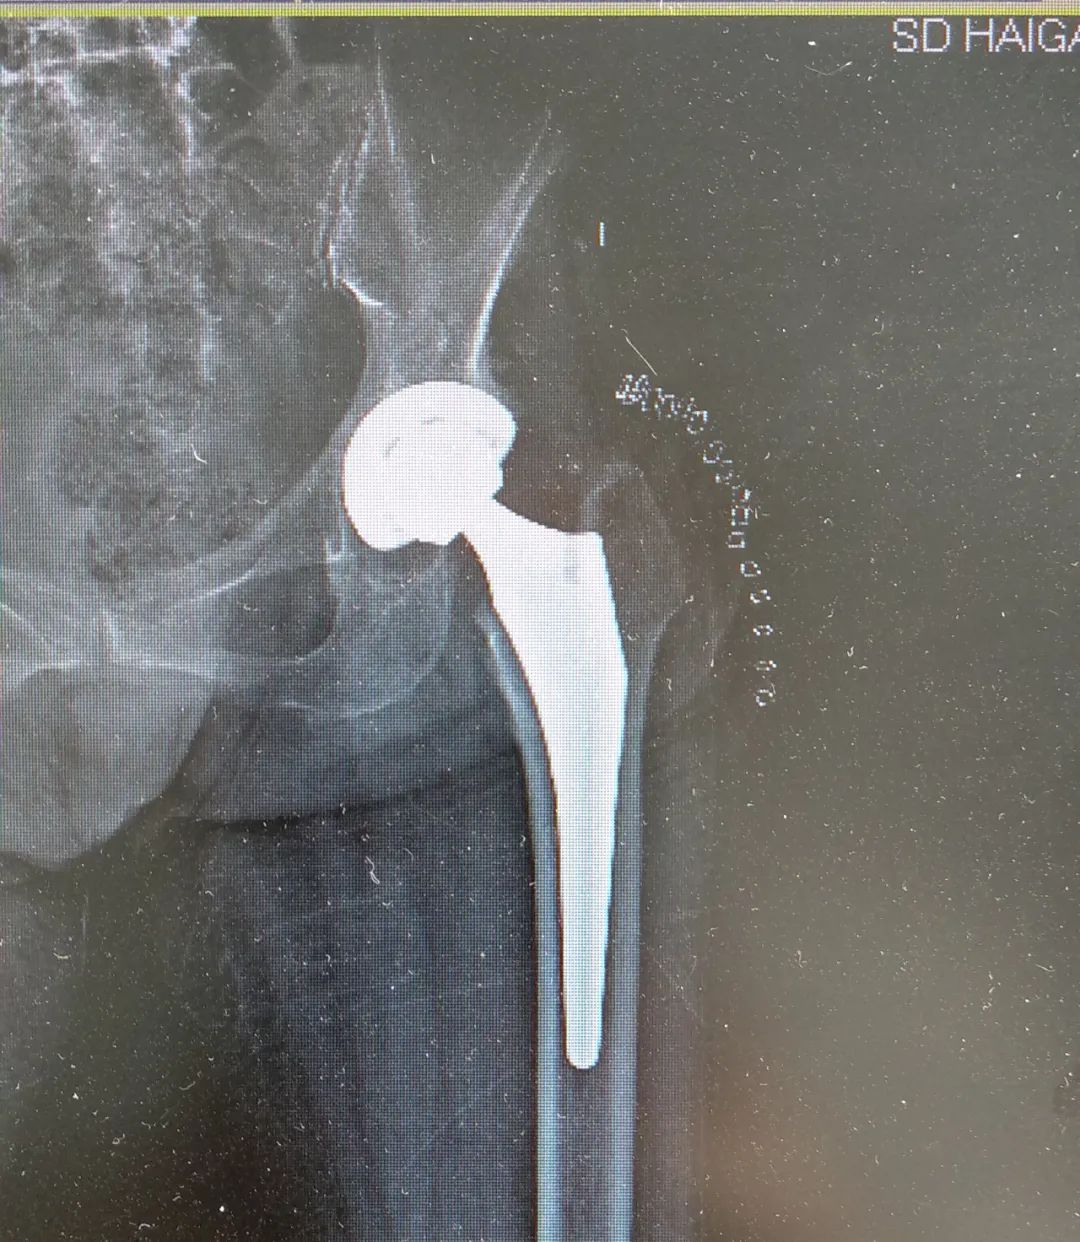

图:术后X线照片

图:麻醉科副主任、副主任医师王兆栋

经过骨外二科医护团队的精心治疗护理,迟老太的病情一天天好转,术后第3天,她已经能够在助行器辅助下负重行走了。家属对海港医院的治疗非常满意,对海港医院骨科精湛的技术水平赞不绝口!